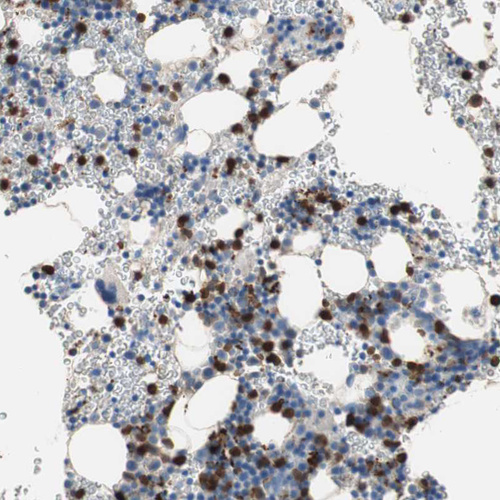

Immunohistochemical staining of human bone marrow shows moderate to strong cytoplasmic positivity in hematopoietic cells.